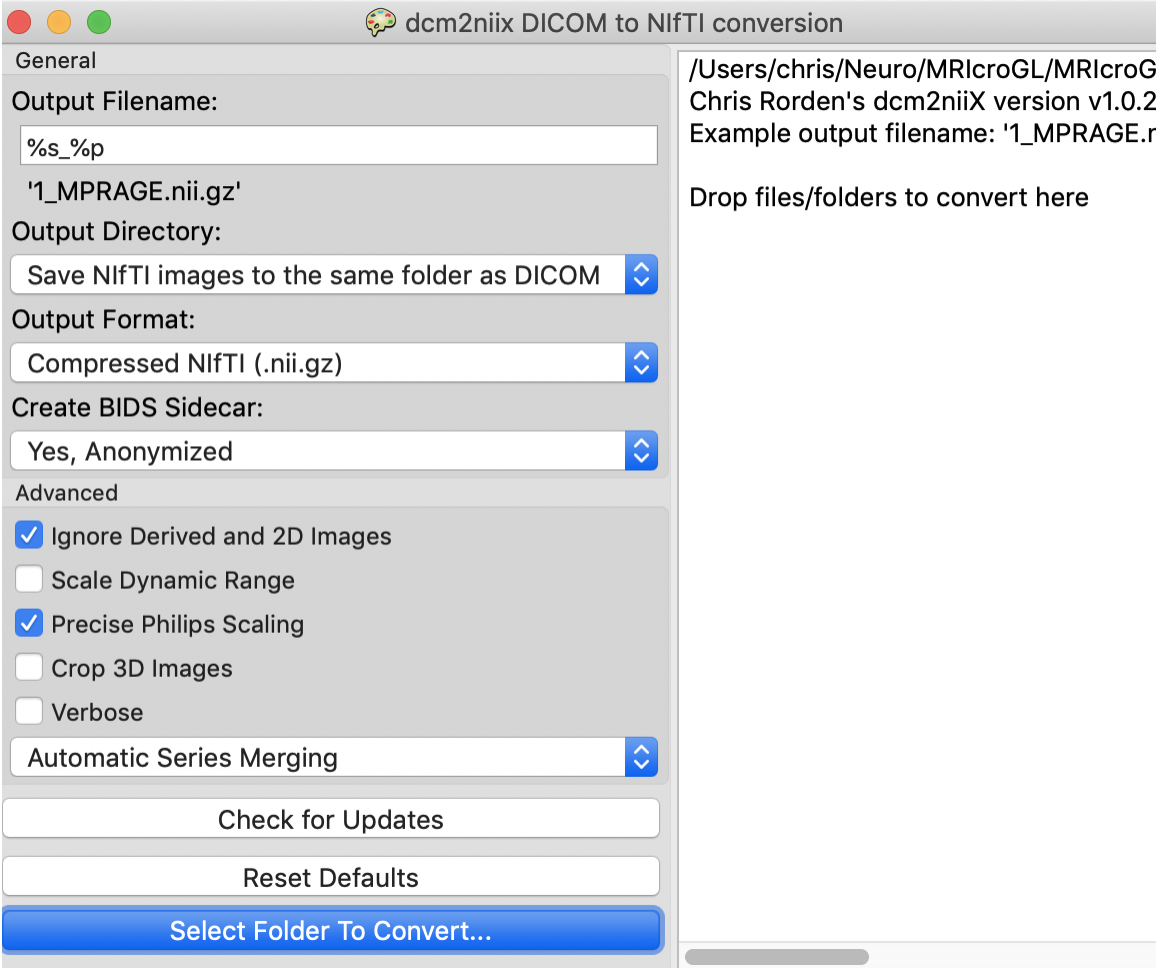

MRIcroGL包括一个简单的图形用户界面,用于控制dcm2niix。启动 MRIcroGL 后,选择 Import/ConvertDICOMtoNIfTI菜单项。

界面如下图所示。

复选框设置输出是压缩(创建.nii.gz文件)还是不压缩(创建.nii文件)。然后,您可以使用图片中描述的格式指定所需的输出文件名。

当您调整所需的输出名称时,软件将显示一个示例,说明您的文件将如何显示。您还可以选择是否要将输出保存到特定的文件夹中,或者是否应该在与输入DICOM文件相同的文件夹中创建NIfTI图像。

最后一步是拖放要转换为应用程序的文件夹。注意,界面总是以交互方式显示命令行,因此,当您通过选择复选框与界面交互时,您正在创建一个文本命令,您可以将其复制并粘贴到您喜欢的脚本中。

注意:我在 mac 中使用 MRIcroGL 转 Nii 时,会提示没有有效的DICOM文件,但是我换成 MRICron 就能成功。奇了怪了,搞不懂,遇到同样问题的话,你就使用 MRICron。

MRICron的下载链接,软件示意图👇